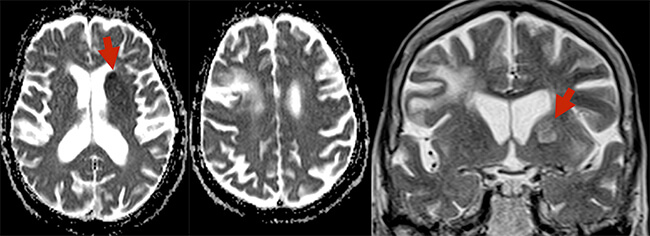

Ακολούθησε αξονική αγγειογραφία με ταχεία έγχυση σκιαγραφικού. Διαπιστώθηκε θρόμβος στον διχασμό της αριστερής έσω καρωτίδος (κόκκινα βέλη)

και καλή παράπλευρη κυκλοφορία που σημαίνει ότι υπήρχε βιώσιμο εγκεφαλικό παρέγχυμα στην κατανομή του αποφραγμένου αγγείου, το οποίο όμως ισχαιμεί (γι´ αυτό και τα βαρειά συμπτώματα της ασθενούς). Η ασθενής βρίσκεται σε άμεσο κίνδυνο να υποστεί μη αναστρέψιμη νέκρωση. Μεταφέρεται άμεσα στον αγγειογράφο.